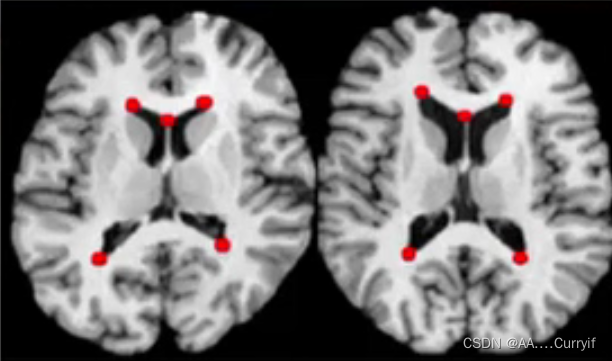

(1) Landmark based

— Indentifying corresponding points in the images and inferring the image transformation

—Types of landmatks:

-Intrinsic: internal anatomical structure

-Extrinsic: artificial objects attached to the patients

—Computing the average or ‘centroid’ of each set of points → translation